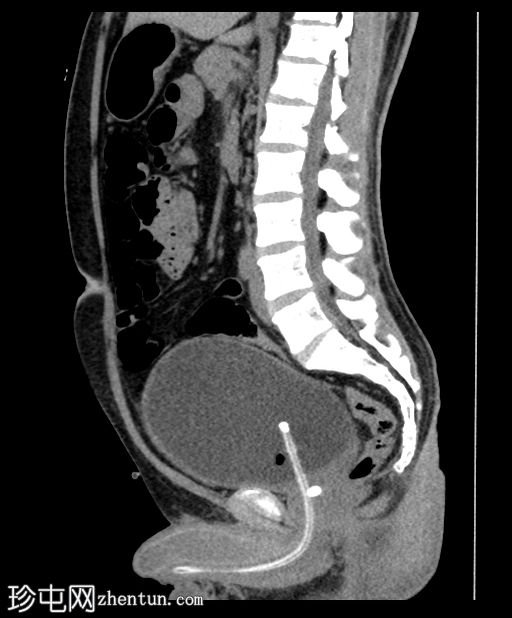

矢状位

平扫

前列腺尿道内可见一枚较大的结石,大小约为10.5 x 13.5 x 7.5 mm(前后径 x 横径 x 头尾径)

轻度肾盂输尿管积水,左侧更为明显

膀胱壁轻度增厚约4 mm,膀胱周围脂肪间隙模糊,提示合并膀胱炎